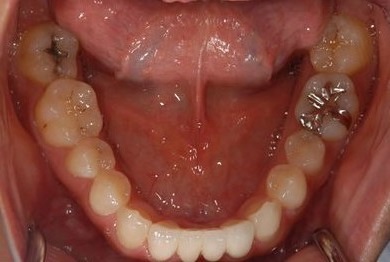

| 性別/年齢 | 女性 / 28歳 | ||||||||||||||||||||||||||||||||

| 主訴 | 下前歯の色が気になるので、ホワイトニングかセラミック治療できれいにしたい。(下前歯2本は乳歯でした) | ||||||||||||||||||||||||||||||||

| 治療方針 | 下顎前歯、乳歯を抜歯し、セラミック治療にて審美的回復を行う。 | ||||||||||||||||||||||||||||||||

| 治療内容 | エンプレスジルコニアフレームオールセラミッククラウンブリッジ4本 | ||||||||||||||||||||||||||||||||